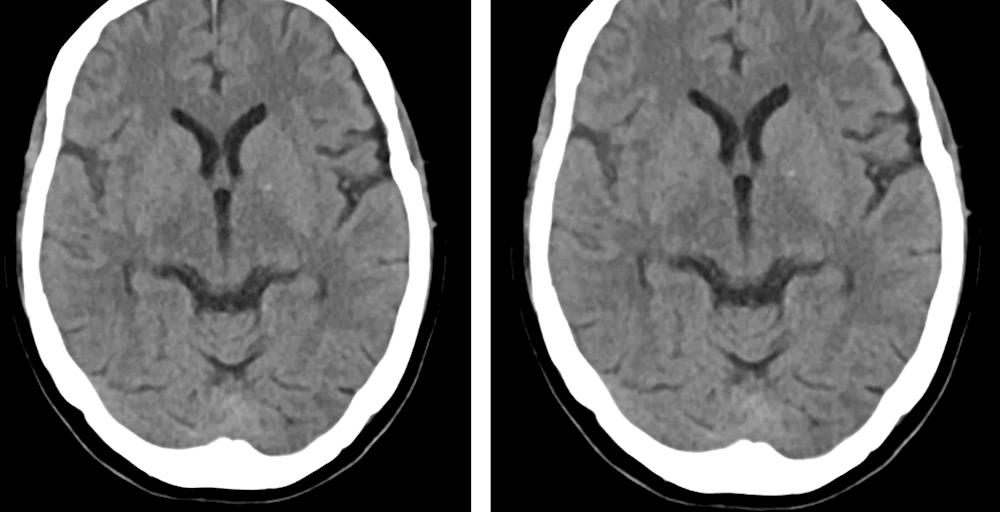

经治疗后,黄阿姨症状消失,恢复正常,复查头颅CT出血灶基本吸收,顺利出院。

出院前复查头颅CT图片,出血已基本消失